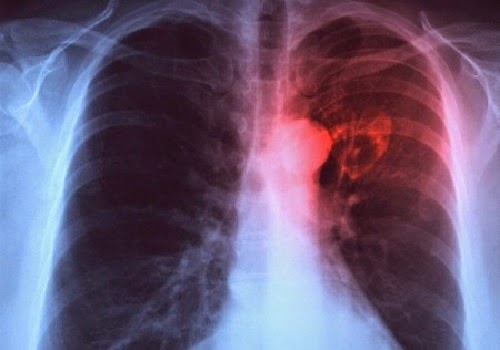

CANCRO AL POLMONE: AUMENTANO I CASI TRA LE DONNE

I dati emersi dal volume indicano un netto calo delle morti causate dal cancro, in particolare nel ventennio che va dal 1996 al 2014 queste sono diminuite del 14% fra gli uomini e del 10% fra le donne. Da sottolineare però un punto allarmante dell’indagine, sono aumentati del 61% i casi di donne colpite da cancro al polmone.